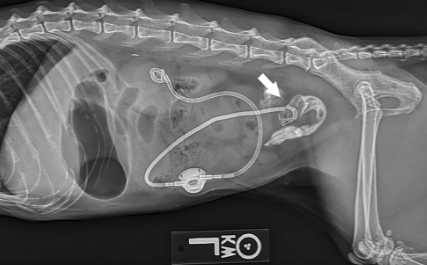

이번에 논문으로 나오는 부작용은 SUB를 장착한 고양이에서 이 SUB 튜브가 유주하여 장분절로 꼽혀버린 상태에 대한 논문이다.

말로 설명하면 무슨 말도 안되는 소린가 싶기에 논문에 나오는 예시 사진을 보면 아래와 같다.

초음파로 plication 까지 발생한 환자의 영상이나 이는 운이 좋아 진단하는 case로 생각되고 실제 진단이 쉽지는 않을것이다.

flushing bell을 통해 조영제를 주입하면 이렇게 migration된 끝단이 확인될 수 있으니 이 방법으로 체크해 보는게 추천된다.